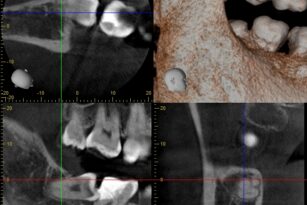

左下奥歯が腫れた 20代 男性 親知らずの抜歯

| 通院目的 | 右下の虫歯と親知らずの腫れ | ||

| 診断 | 虫歯と親知らずの炎症 | ||

親知らずが腫れている | ||

| 通院期間・回数 | 1週間・3回 | ||